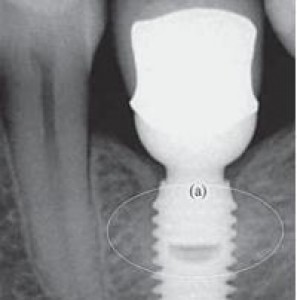

Implantologia 25 Febbraio 2013

Il platform switching riduce almeno di 1/3 la perdita di osso intorno agli impianti e conferma gli effetti positivi già segnalati in letteratura. Questa in sintesi la conclusione di uno studio...